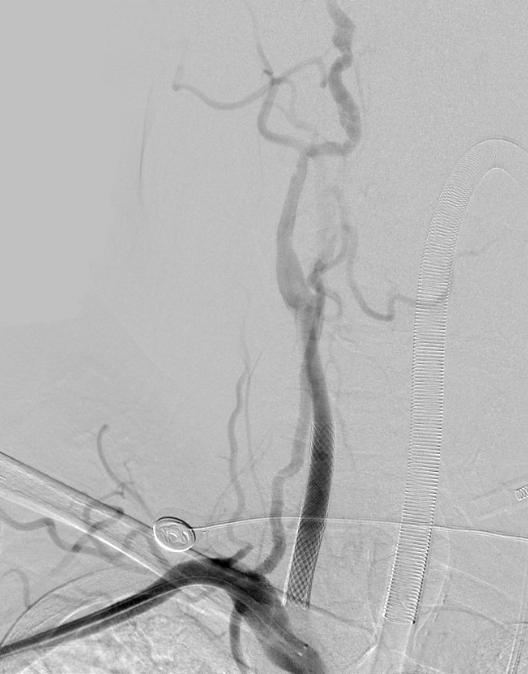

在此基础上,进一步卓越长节段夹层,精确参加右侧颈总动脉真腔,植入支架建造血管内膜扯破,胜仗复原脑部血流,昭彰改善脑低灌输景况,为后续主动脉夹层外科手术创造了安全条目,获取了可贵的时代窗口,也为患者神经功能的复原奠定了基础。

△右颈总动脉术前术后对比

△主动脉夹层术前术后对比